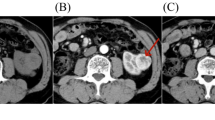

All CT images were resampled into isotropic voxel size (1 mm × 1 mm × 1 mm). The enhanced-CT scan images of 190 cases (in the cortical phase) were loaded into the ITK-SNAP software. The region of interest (ROI) was segmented by two diagnostic physicians with 15–20 years of working experience. To verify the consistency of ROI against the intra- and inter-observer delineation variations, the delineation was repeated on 40 patients (20 patients with ccRCC and 20 with non-RCC who were randomly chosen) by the same radiologist (Reader 1 with 15 years’ experience in urologic imaging) for intra-observer assessment and by the other radiologist (Reader 2 with 20 years’ experience in urologic imaging) for interobserver assessment. When the intraclass correlation coefficient (ICC) was greater than 0.75, it was considered in good agreement, and the remaining image segmentation was performed by reader 1. The delineation principles of ROI (Fig. 3) were 0–1 mm in the medial margin in the cortical phase was selected for delineation with the ROI being delineated layer-by-layer to obtain the volume of the interest (VOI).

Renal cell carcinoma. (A) A 59-year-old man had cortical phase of papillary renal cell carcinoma (RCC) on computed tomography (CT) enhancement (ROI with dotted line). (B) A 62-year-old woman had cortical phase of clear cell RCC on CT enhancement (ROI with dotted line). (C) A 71-year-old man had cortical phase of chromophobe RCC on CT enhancement (ROI with dotted line).